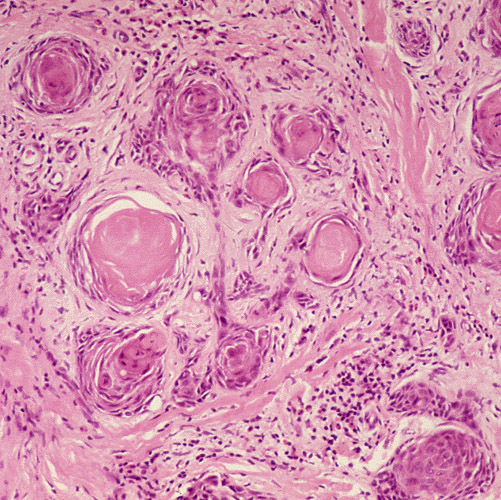

Squamous cell carcinoma